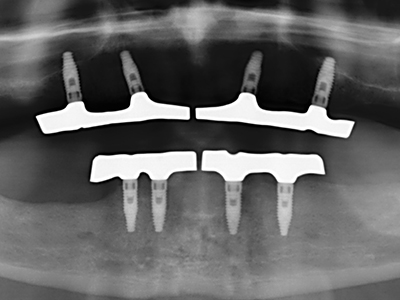

Knochengewebe ist nicht nur rein mineralisch, sondern auch in wesentlichen Anteilen aus Kollagenfasern aufgebaut. Dies gewährleistet neben einer guten Druckfestigkeit eine gewisse Flexibilität, welche für die Durchführung von Augmentationen genutzt werden kann. Bei der klassischen Expansionsplastik im Sinne eines Bone Splittings wird der atrophierte Kieferkamm in seiner Längsachse gespalten und nach Erreichen einer ausreichenden Osteotomietiefe vorsichtig aufgedehnt (Abb. 13-16), idealerweise ohne den Kiefer wesentlich zu deperiostieren (Brugnami, Caiazzo et al. 2014, Stricker, Fleiner et al. 2014). Bewährt haben sich Schrauben- und Plattensysteme mit zunehmender Expansionsdistanz, um die beiden Knochenlamellen unterhalb der Bruchschwelle voneinander zu distanzieren. In der Regel werden Restknochenbreiten von mindestens 3-4 mm gefordert (Chiapasco, Zaniboni et al. 2006), um eine ausreichende Flexibilität und knöcherne Bedeckung der einzubringenden Implantate zu gewährleisten. Ggf. kann eine ein- oder beidseitige vertikale Entlastungsosteotomie die Flexibilität verbessern. Als Alternative zur klassischen Technik wurde eine Kombination mit weiteren augmentativen Techniken vor allem auf der bukkalen Seite beschrieben.

Mittels Piezosägen erfolgt die Anlage des Splittings besonders schonend und ohne wesentliche Dimensionsverluste, so dass sich keine signifikanten Unterschiede von Implantaten im gesplitteten Kiefer im Vergleich zum nicht defizitären Alveolarkamm gezeigt haben (Chiapasco, Zaniboni et al. 2006, Danza, Guidi et al. 2009). Gerade beim lokal begrenzten und tiefen Splitting ist jedoch stets auf eine ausreichende Wasserkühlung zu achten, um thermische Belastungen in den apikalen Osteotomiebereichen zu vermeiden.